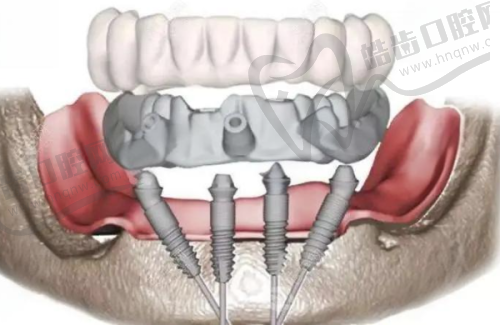

诊疗项目 : 种植牙,单颗种植,多颗种植,半口种植,全口种植,韩国登腾Dentium种植牙,韩国奥齿泰Osstem种植牙,瑞典诺贝尔Nobel种植牙,瑞士ITI种植牙,韩国安美齿IBS,美国3I种植体,德国ICX,美国皓圣Hiossen,韩国DIO,华西cdic,美国百康Bicon,德国xive,德国Camlog,瑞典astra,韩国登特斯Dentis,韩国美格真MegaGen,德国贝格Bego,德国ANKLAS种植牙,瑞士士卓曼Straumann,意大利西泰克C-Tech,韩国仕诺康Snuc,美国杰美Zimmer,国产莱顿BLB,国产威高WEGO,以色列丹特因Dentin,以色列柯特斯CORTEX,穿颧种植,all-on-4种植牙,穿翼板种植牙技术,即刻种植牙,瑞士百丹特种植体,法国安卓健Anthogyr种植体,上颌窦提升术,韩国纽百特NeoBiotech种植体,美国百好瑞biohorizons种植体

周毅医生在种植牙领域有着极高的造诣。他是口腔种植和口腔修复两个首批国内临床重点专科的骨干成员,在医院先开展了穿颧种植等一系列高难度手术和治疗项目,折断种植体螺丝取出技术处于国内外领跑地位。